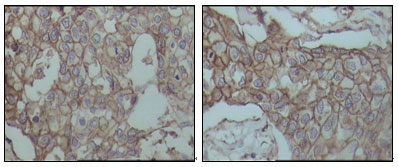

Figure 3: Immunohistochemical analysis of paraffin-embedded human breast carcinoma tissues, showing membrane localization with DAB staining using CD44 mouse mAb. |